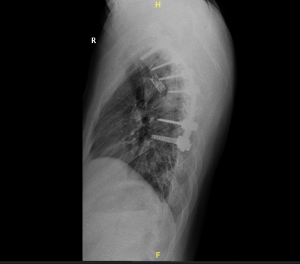

Semua disesuaikan dengan situasi dan kondisi pasien. Pada kasus spinal TB yang mengubah postur normal menjadi lebih bungkuk, terkadang perlu operasi pemasangan implan agar postur kembali normal.

Jika ruas tulang belakang sudah hancur oleh infeksi Tuberculosis ini, diperlukan pemasangan implan pengganti dari ruas tulang tersebut. Artinya TB tersebut sudah dialami dalam jangka yang lama tanpa pengobatan, dan perlu segera dilakukan tindakan. Dalam kasus ini biasanya sudah mulai ada fungsi saraf yang tidak normal seperti, nyeri yang menjalar ke kaki, nyeri ketika berjalan, dsb.